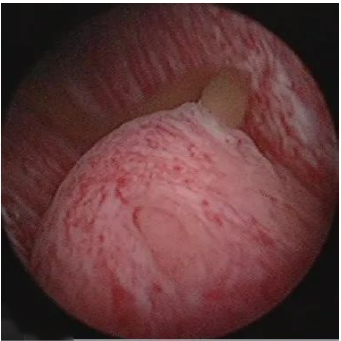

图二:射精管口排出的混浊精液(炎症合并出血)